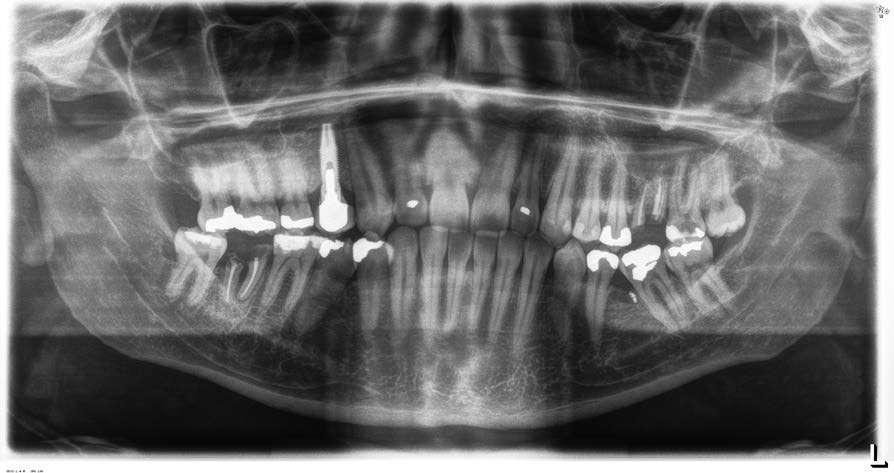

ELEVACIÓN TRANSCRESTAL CON IMPLANTES CORTOS UNITARIOS.

SERIE DE CASOS

Los implantes cortos y extracortos son una alternativa para las zonas de atrofia ósea alveolar a nivel posterior donde existe una altura reducida para la inserción directa de implantes de mayor longitud. En este caso la elevación de seno convencional o por abordaje lateral ha sido siempre la técnica a emplear hasta la llegada de estos implantes y la técnica de elevación transcrestal. A lo largo de este artículo se presentan una serie de casos con los que se concluye que los implantes unitarios cortos o extracortos, unidos a la técnica de elevación crestal, pueden ser una apuesta terapéutica segura y predecible cuando se emplean protocolos cuidadosos de inserción y de rehabilitación protésica.

La técnica de elevación de seno transcrestal nace como una alternativa a la elevación de seno convencional por abordaje lateral para reducir los efectos secundarios así como las posibilidades de fracaso por aparición de complicaciones, que son mucho más frecuentes en el abordaje convencional1-2. La técnica ha evolucionado desde su concepción por Summers en los años 90, generándose instrumentos para poder lograr un abordaje menos invasivo y más simple para el cirujano que lo lleva a cabo, pero la esencia del procedimiento continúa siendo la misma3. Se genera una perforación en la cresta alveolar por la que se accede a la membrana sinusal para ser elevada y poder insertar posteriormente implantes en la misma fase quirúrgica, con o sin material de relleno, en función de las características del lecho receptor y las preferencias del profesional4-6. La unión de los implantes cortos y extracortos a la técnica de abordaje transcrestal del seno abrió una nueva ventana de posibilidades para realizar procedimientos cada vez menos invasivos y tratar casos de atrofia severa con intervenciones sencillas y predecibles7-8. En las primeras fases de empleo de esta técnica unido a los implantes cortos se establece un límite de al menos 5 mm de hueso residual en altura para garantizar una correcta estabilidad del implante y por lo tanto el éxito del procedimiento9-10. Según se avanza en el uso de la técnica y surgen nuevas longitudes de implantes, como los implantes ultracortos actuales, con longitudes de 4,5 mm se modifican los protocolos. Esta modificación se basa en el concepto de estabilidad primaria tridimensional

(en toda la anchura del alveolo) y no solo en la altura del hueso remanente residual. De este modo en longitudes menores de 5 mm si utilizamos un correcto protocolo de fresado y posicionamos el implante de forma correcta en el plano tridimensional podemos lograr una estabilidad que nos permita alcanzar el éxito de tratamiento en casos donde la indicación clara hace unos años habría sido el abordaje lateral convencional10-12. Posteriormente, varios estudios han apoyado esta tesis, identificando la importancia de la anchura entre las paredes del seno, que es más crítica que la altura de hueso residual. Una anchura entre las paredes vestibular y palatina del seno menor de 12 mm nos garantiza una formación de hueso mayor que en distancias superiores, siendo estos 12 mm la distancia crítica que marca la diferencia entre lo que podemos considerar un seno “estrecho” o favorable y uno “ancho” o desfavorable8,13-15. Aun con toda esta información y con un protocolo de fresado estandarizado y adaptado a las necesidades de cada paciente existen situaciones como las reposiciones unitarias que cuando son realizadas con elevación transcrestal presentan mayor riesgo tanto en su fase quirúrgica como en la posterior carga16,17. Esta situación se da en un menor porcentaje de casos, debido a que una pérdida unitaria, no suele generar un defecto en altura de grandes dimensiones, si se conservan piezas adyacentes que mantienen la altura ósea en mesial y distal de la pieza ausente. A pesar de no ser una situación muy frecuente, cuando nos enfrentamos a ella, poder disponer de una técnica poco invasiva

Material y método

Fueron revisadas historias clínicas de forma retrospectiva de los implantes insertados en el segundo semestre del año 2015 y primer trimestre del año 2017, de tal forma que puedan tener un seguimiento en el tiempo tras la carga elevado, para identificar aquellos casos implantes cortos y extra-cortos insertados de forma unitaria en zonas de maxilar posterior con altura ósea residual menor de 5 mm y con la técnica de elevación transcrestal. Todos los pacientes fueron estudiados antes de la inserción de los implantes mediante modelos diagnósticos, exploración intraoral y realización de un TAC dental (Cone-beam) analizado posteriormente mediante un software específico (BTI-Scan II). Antes de la inserción de los implantes se utilizó una pre-medicación antibiótica consistente en amoxicilina 2 gr vía oral una hora antes de la intervención y paracetamol 1 gramo vía oral (como analgésico). Posteriormente los pacientes prosiguieron con un tratamiento de amoxicilina 500-750 mg vía oral cada 8 horas (según peso) durante 5 días. Los implantes fueron colocados por un mismo cirujano, mediante la técnica de fresado biológico, a bajas revoluciones, sin irrigación17-19. El fresado final de la cortical sinusal se realiza con la fresa de corte frontal (ideada para esta técnica) que nos permite la retirada del suelo del seno maxilar sin dañar la membrana de Schneider12. Una vez la membrana es accesible mediante la perforación crestal se despega, colocándose el injerto óseo y posteriormente se inserta el implante con el motor quirúrgico fijado a 25 Ncm y 25 rpm finalizando la inserción del implante con la llave dinamométrica. El fresado se adapta para lograr una correcta estabilidad primaria conociendo la densidad de la zona y el volumen óseo residual. El implante eleva lentamente la membrana a la vez que es insertado en el neo-alveolo.

los pacientes acuden cada 6 meses a la realización de radiografías panorámicas de control y sobre estas radiografías se realizan las mediciones necesarias para comprobar la estabilidad y pérdida ósea crestal de los implantes. Una vez obtenida la radiografía en formato digital es calibrada mediante un software específico (Sidexis measure) a través de una longitud conocida en la radiografía como es el implante dental. Una vez introducimos la medida de calibración, el programa informático realiza un cálculo basado en esta medida para eliminar la magnificación, pudiendo realizar mediciones lineales exentas de este error.

El implante fue la unidad de análisis para la estadística descriptiva en cuanto a la localización, dimensiones del implante, y mediciones radiográficas. El paciente fue la unidad de medida para el análisis de la edad, sexo y la historia médica. La variable principal fue la supervivencia del implante y como variables secundarias se registraron la pérdida ósea mesial y distal y la presencia de complicaciones quirúrgicas o protésicas.

Fueron reclutados 11 pacientes en los que se insertaron 11 implantes que cumplieron los criterios de inclusión. 6 de los pacientes fueron mujeres, con una media de edad en el grupo de 62 años (+/- 6,7). Ninguno de los pacientes eran fumadores. La localización más frecuente en los implantes estudiados fue para la zona de la pieza dental 16 (54,5%) seguida de la pieza 26 (27,3%) y finalmente la localización menos frecuente fue para la pieza 27 (18,2%). La longitud predominante de los implantes insertados fue de 7,5 mm en el 72,7% y de 6,5 mm en el 27,3% de los casos. En cuanto al diámetro, el más frecuente fue el de 5,5 mm con un rango que osciló entre los 5 y los 6,25 mm. Los diámetros y longitudes de los implantes incluidos en el estudio se recogen de forma detallada en la figura 1.

Figura 1. Implantes incluidos en el estudio según su diámetro y longitud.

1

Figura 2. Imagen inicial del caso donde podemos observar un resto radicular en posición 26 que debe ser extraído para posterior colocación de un implante dental.

La altura media de la cresta en los implantes estudiados fue de 3,75 mm (+/-1,04) con un rango de entre 2 y 4,90 mm. El tiempo medio de seguimiento de los implantes fue de 60 meses (+/- 9,3). La media de la pérdida ósea mesial de los implantes fue de 0,69 mm (+/- 0,69) y la media de la pérdida ósea distal fue de 0,63 mm (+/- 0,39). Todos los implantes fueron rehabilitados en dos fases y

2

todos ellos fueron ferulizados a otros implantes en la rehabilitación. Las prótesis colocadas sobre los implantes fueron atornilladas mediante transepitelial Unit en el 100% de los casos. Durante el período de seguimiento no se registró ningún fracaso de implante ni eventos adversos en la prótesis. En la imagen 2 – se muestra uno de los casos incluidos en el estudio.

Figuras 3 y 4 . Corte del Cone-beam dental tras la exodoncia y regeneración del alveolo con Endoret-PRGF cuatro semanas después. Podemos observar la atrofia ósea en sentido vertical de la zona con una altura máxima de 3 mm. La planificación como podemos visualizar será para la realización de una elevación transcrestal mínima y la colocación de un implante extracorto.

Figuras 5 y 6. Inicio de fresado de la cortical inferior del seno maxilar con la fresa de corte frontal.

Figuras 7 y 8. Despegamiento de la membrana para comenzar la elevación transcrestal.

Figuras 9 y 10. Inserción de membrana de fibrina como material de relleno en el neo-alveolo y colocación del implante.

Figura 11. Colocación de la corona con el transepitelial unitario 6 meses tras la cirugía.

Figura 12. Mantenimiento de la altura ósea lograda y de la estabilidad del implante al año de carga visualizada en cone-beam.

Figura 13. Estabilidad del tratamiento a los 7 años. No existe pérdida ósea asociada ni problemas relacionados con la prótesis.

Los implantes cortos y extracortos rehabilitados de forma unitaria en el maxilar, mediante abordaje transcrestal han sido una opción terapéutica para evitar cirugías mas invasivas en los pacientes del presente estudio y por lo tanto disminuir la morbilidad de la técnica convencional, que hubiese precisado una elevación de seno por abordaje lateral. Uno de los principales inconvenientes reportados en la literatura es la menor predictibilidad de estos implantes cortos cuando se insertan en el maxilar superior posterior comparados con los implantes considerados “de longitud convencional” unido a las técnicas reconstructivas20-22. En algunos estudios se reportan mayor porcentaje de complicaciones y fracasos20-22, mientras que en otros estudios la incidencia de estos eventos es similar o a favor de los implantes cortos12,18,23. El principal reto de estos casos mostrados en el presente estudio ha sido lograr la estabilidad con un implante unitario, tanto

inicial, como a largo plazo, en un hueso con extrema reabsorción vertical y un implante de longitud disminuida (como son los implantes cortos y extracortos). Aun así, siguiendo un cuidadoso protocolo de inserción y de fresado basado en las características del lecho receptor y en la morfología del implante a insertar se ha logrado una resolución de todos los casos con un 100% de supervivencia tanto en los implantes como en las prótesis12,17-19. Esta diferencia entre los distintos protocolos puede ser un punto diferencial en los estudios donde se han reportado tasas de fracaso superiores para cohortes como la analizada en nuestro grupo de estudio.

Conclusiones

Los implantes unitarios cortos o extracortos unidos a la técnica de elevación crestal pueden ser una apuesta terapéutica segura y predecible cuando se emplean protocolos cuidadosos de inserción y de rehabilitación protésica.

Resumen

Introducción: los implantes cortos y extracortos son una alternativa para las zonas de atrofia ósea alveolar a nivel posterior donde existe una altura reducida para la inserción directa de implantes de mayor longitud. En este caso la elevación de seno convencional o por abordaje lateral ha sido siempre la técnica a emplear hasta la llegada de estos implantes y la técnica de elevación transcrestal. Material y métodos: fueron revisadas historias clínicas de forma retrospectiva aquellos casos implantes cortos y extra-cortos insertados de forma unitaria en zonas de maxilar posterior con altura ósea residual menor de 5 mm y con la técnica de elevación transcrestal. El fresado final de la cortical sinusal se realiza con la fresa de corte frontal (ideada para esta técnica) que nos permite la retirada del suelo del seno maxilar sin dañar la membrana de Schneider. Los pacientes acuden cada 6 meses a la realización de radiografías panorámicas de control y sobre estas radiografías se realizan las mediciones necesarias para comprobar la estabilidad y pérdida ósea crestal de los implantes. La variable principal fue la supervivencia del implante y como variables secundarias se registraron la pérdida

ósea mesial y distal y la presencia de complicaciones quirúrgicas o protésicas.

Resultados: fueron reclutados 11 pacientes en los que se insertaron 11 implantes que cumplieron los criterios de inclusión. La longitud predominante de los implantes insertados fue de 7,5 mm en el 72,7% y de 6,5 mm en el 27,3% de los casos. En cuanto al diámetro, el más frecuente fue el de 5,5 mm con un rango que osciló entre los 5 y los 6,25 mm. La altura media de la cresta en los implantes estudiados fue de 3,75 mm (+/-1,04) con un rango de entre 2 y 4,90 mm. El tiempo medio de seguimiento de los implantes fue de 60 meses (+/- 9,3). La media de la pérdida ósea mesial de los implantes fue de 0,69 mm (+/- 0,69) y la media de la pérdida ósea distal fue de 0,63 mm (+/- 0,39). Durante el período de seguimiento no se registró ningún fracaso de implante ni eventos adversos en la prótesis.

Conclusiones: los implantes unitarios cortos o extracortos unidos a la técnica de elevación crestal pueden ser una apuesta terapéutica segura y predecible cuando se emplean protocolos cuidadosos de inserción y de rehabilitación protésica.